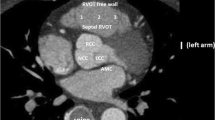

Proximity of the coronary vessels to the posteroseptal RVOT. a Ablation catheter in the posteroseptal RVOT close to the origin of the left main coronary artery (LM) and the left anterior descending artery. b Reconstructed computed tomographic image showing the proximity of the coronary arteries and the posteroseptal RVOT. RAO right anterior oblique; LAO Left anterior oblique; RVOT right ventricular outflow tract, AIC-GCV anterior interventricular vein–great cardiac vein; LV left ventricle; RV right ventricle; LCX left circumflex artery; LAD left anterior descending artery; GCV great cardiac vein